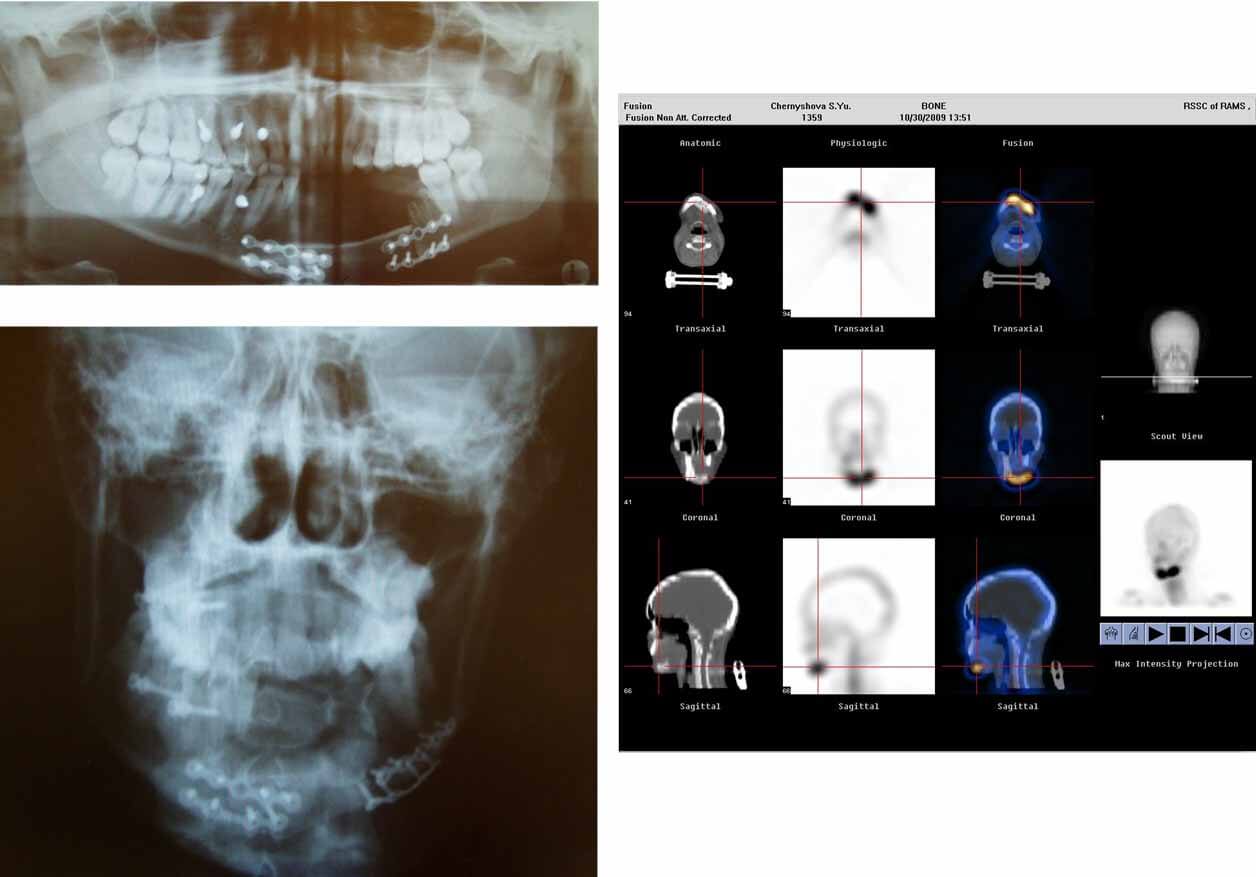

Использование 3D-анализа планирования и моделирования CAD/CAM технологии, робототехники, получение твердотельных моделей лица и лицевого скелета – дает возможность увидеть результат лечения и операций еще до их проведения.

Реабилитация пациента с Постонкологическим деффеком носа, с атрофией мягких тканей после лучевого лечения

Постонкологический деффект носа, с атрофией мягких тканей после лучевого лечения